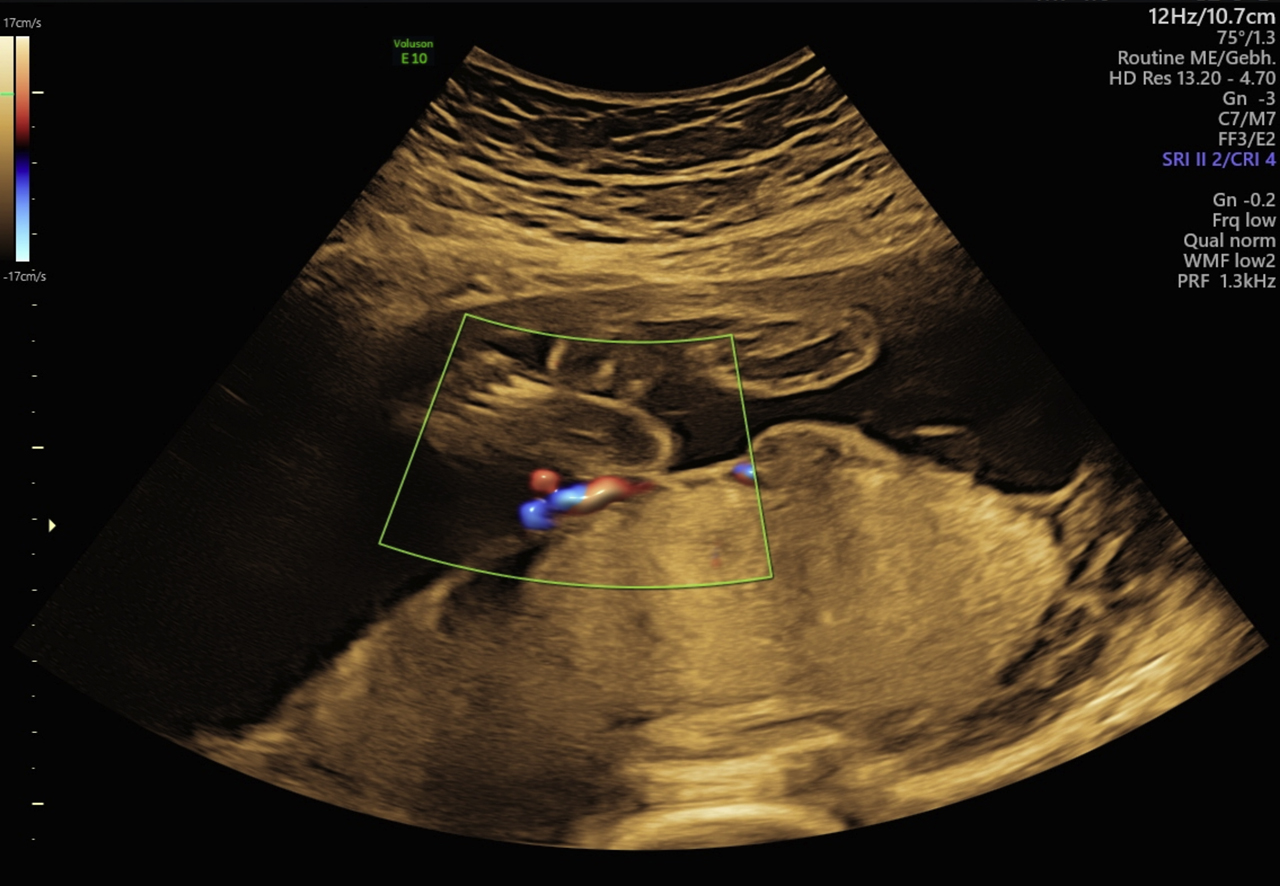

We report a case of a growth restricted fetus caused by a circumvallate placenta as a rare finding which may be associated with further severe pregnancy complications. It can be diagnosed antepartum by ultrasound screening or as a visual diagnosis after birth (Figures 2 and 3).

Thickened placenta with atypical echogenicity at 28+2 weeks of pregnancy. Arrow: circumvallate margin.

The ultrasound showed a growth restricted fetus with an estimated weight of 815 g (<third percentile) and oligohydramnios. Umbilical blood flow was reduced with an absent end-diastolic flow in the umbilical artery while the blood flow in the uterine artery and in the middle cerebral artery were normal. Fetal movements were present. The placenta appeared enlarged with a spherical shape.

Radiographic features of the circumvallate placenta can be an abnormal placental thickness (>3 cm), a peripheral echodense rim or an irregular placental edge (placental “shelf”). Similar features can also be found in other placental abnormalities: The most important radiographic differential diagnosis is amnion sheets and amniotic bands.